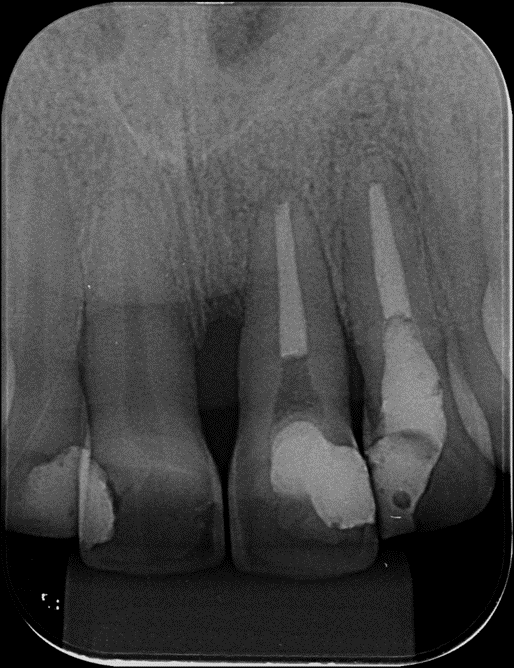

Radiografia Periapical inicial para auxilio no diagnóstico.

Após exame clinico e tomográfico, foi observado comprometimento periodontal e trinca radicular no dente 21.